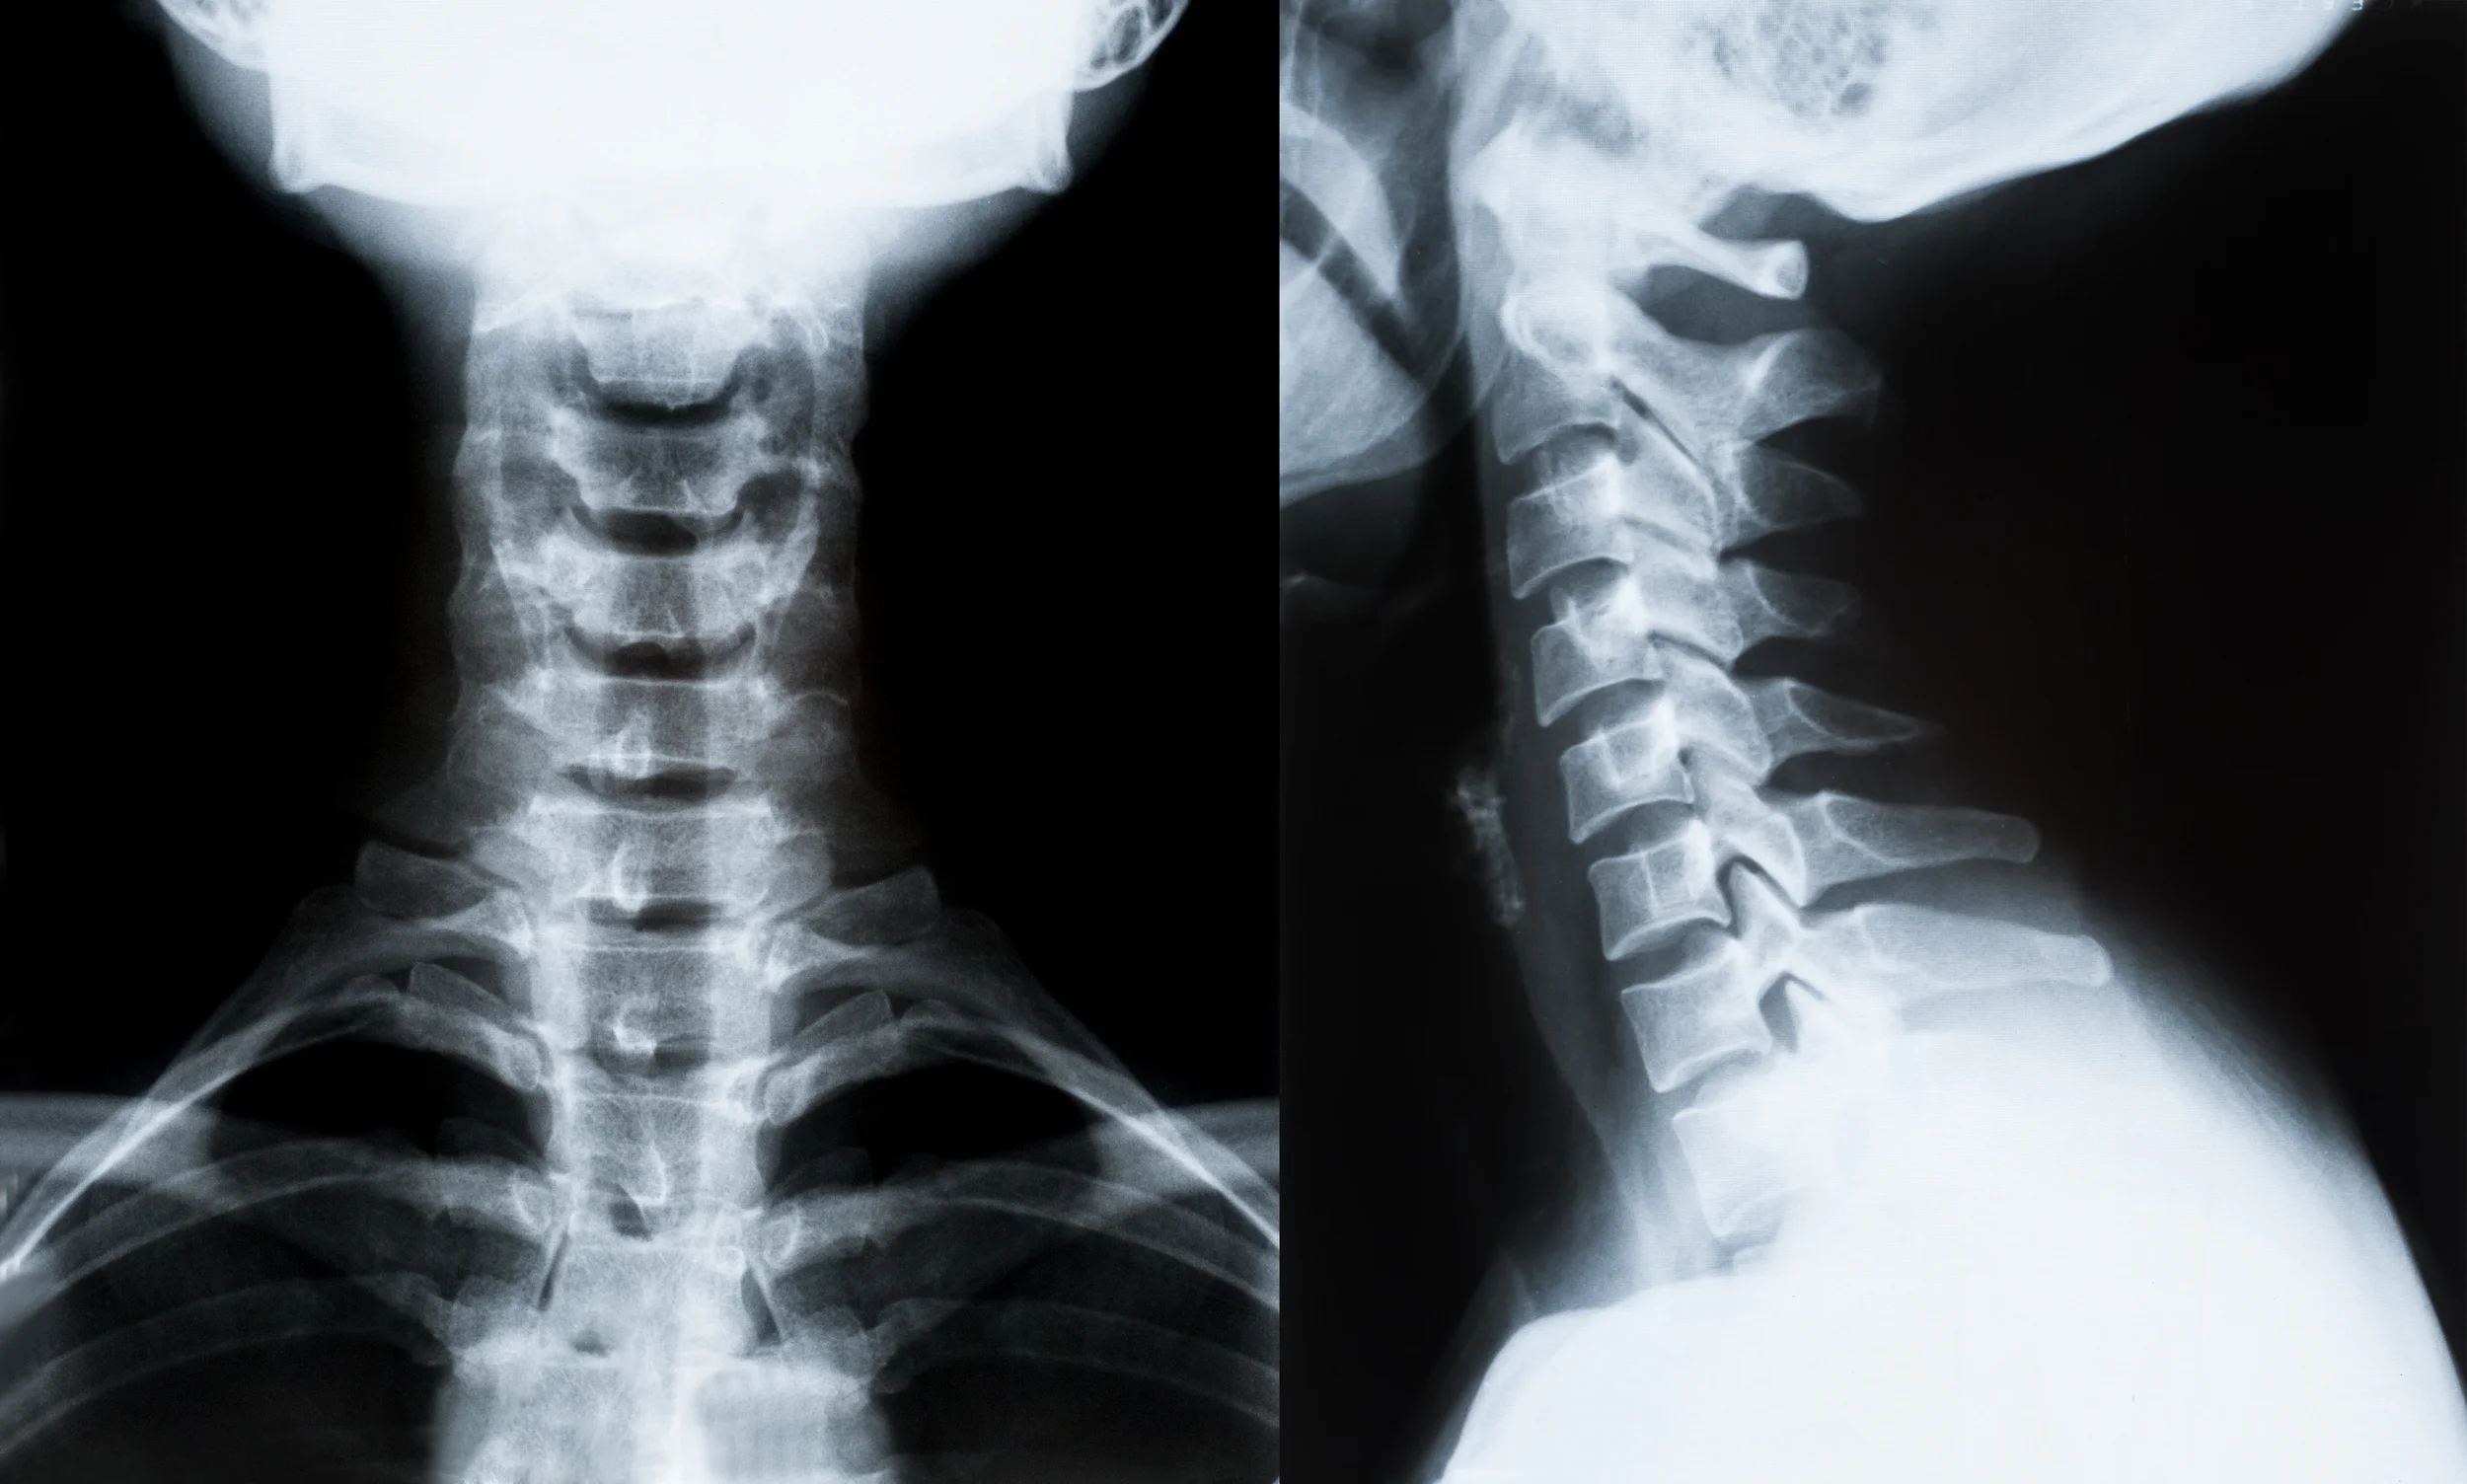

Neck Pain Treatment after a Car Accident - Nashville Chiropractor